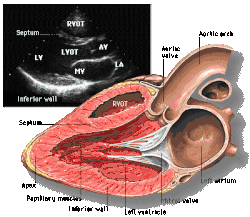

Parasternal long axis (PLAX)

Parasternal long axis

This view is obtained to the left of the sternum and views the heart in its long axis. In this view, the mitral valve, aortic valve, right ventricular outflow tract, base of the left ventricle, and the left atrium can be visible. Angulation in this view can bring the right ventricular inflow tract and tricuspid valve into view, and angulation the opposite way can bring the pulmonary valve into view.

In this view, it is possible to appreciate the long-axis cross section of the mitral and aortic valves. The classic "hockey stick" shape of rheumatic mitral stenosis can be appreciated in this view. However, the angle of the probe with these valves can lead to under-appreciation of valve dysfunction.

The parasternal long view of the pulmonary valve is the only view of the posterior leaflet.

Structures visible:

• Anterior septal and inferior lateral walls of the left ventricle

• Left atrium

• Mitral valve in long-axis with chordae

• Aortic valve in long-axis

• Tricuspid valve in long-axis (angulated) and right ventricular inflow tract

• Pulmonary valve in long-axis (angulated) and right ventricular outflow tract

Measurements in this view can be used to quantify the heart:

• Left ventricular size and wall thickness

• Left atrial linear dimension (as opposed to area)

• Left ventricular outflow tract diameter (used to calculate aortic valve area by the continuity equation)

• Aortic annulus, sinus of Valsalva, and aortic root sizes

• Color doppler of all four valves

• Spectral doppler of tricuspid and pulmonary valves